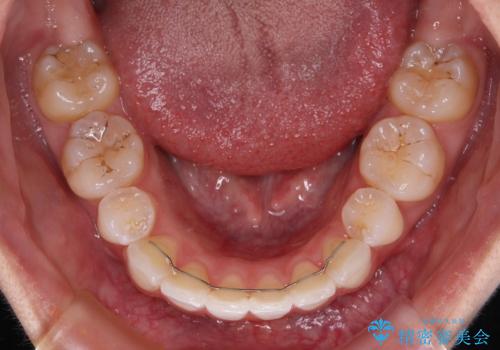

- 矯正装置

- インビザライン・モデレート

- 治療期間

- 1年5ヶ月

インビザライン・モデレートは、製作できるアライナーの枚数に制限があるため、移動可能な量に限りがあるものの、インビザライン・ライトよりも枚数が多いため、幅広い症例に対応可能です。